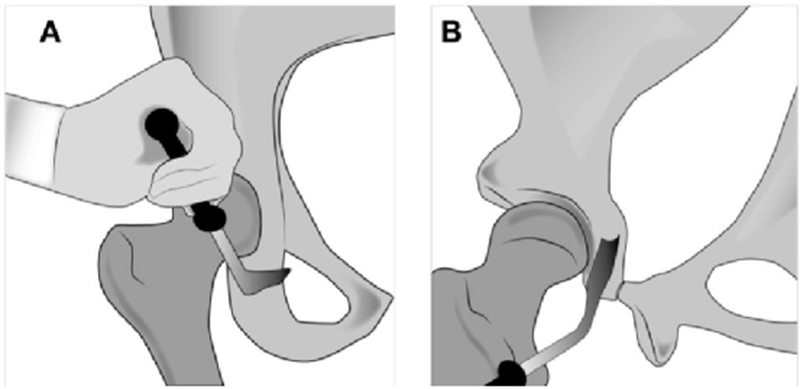

A.图显示用倾斜的Ganz骨刀进行髋臼下截骨。B.后柱的侧视图,显示向坐骨棘倾斜的不完整坐骨截骨。需要多次内侧和外侧击打确认截断整个厚度的坐骨。在截骨过程中伸展下肢,保护坐骨神经

A.耻骨截骨线位于耻骨跟部内侧几毫米处向内倾斜。B.内侧骨撬插入耻骨,近端与远端骨撬插入闭孔,以保护闭孔神经血管束。虚线显示截骨的位置。

A.图示髋臼上截骨,其指向坐骨大切迹,在骨盆缘1cm处停止。B.坐骨截骨,沿骨盆內缘保留后柱截骨。

A.后柱截骨。B.成角骨刀截断残留连接处,截骨块充分游离。C.髂骨斜位透视图显示截骨线。D.游离截骨块